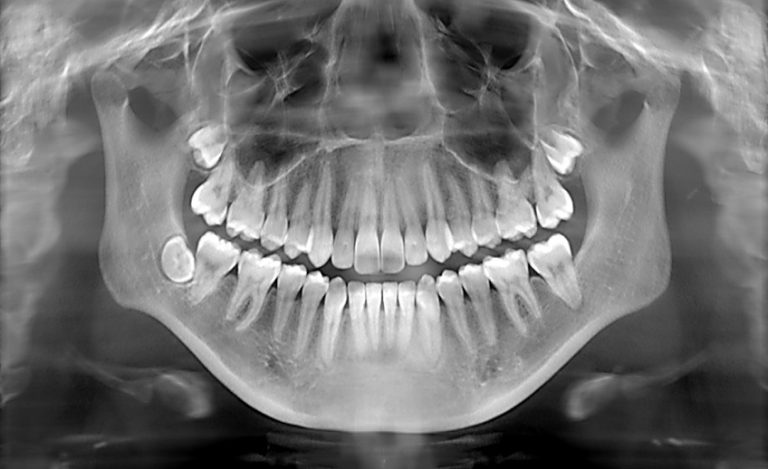

How safe are dental X-rays? Exposure to all sources of radiation — including the sun, minerals in the soil, and.....